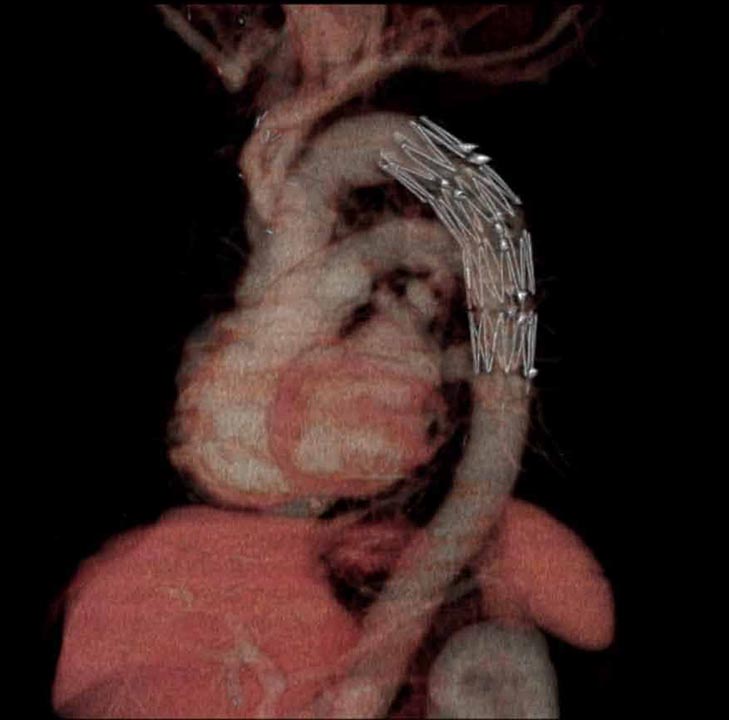

- 大動脈ステントグラフト挿入後